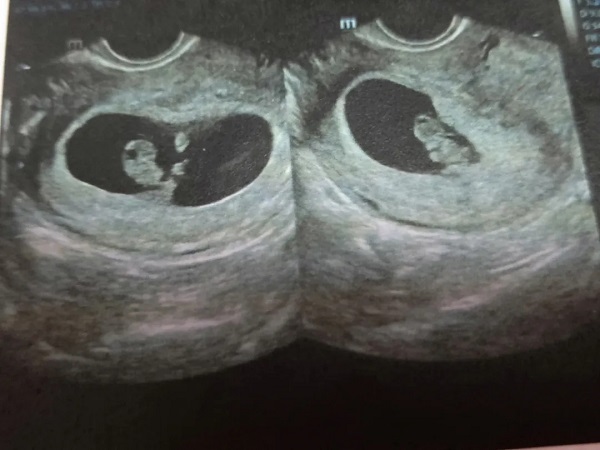

怀孕多久看孕囊形状知道是男是女?

到底肚子里的宝宝是男孩还是女孩,这是很多准爸爸和准妈妈都很关心的问题,民间也有很多预测性别的方法,不过相对于流传的生男生女计算公式,其实通过B超检查后,观察孕囊..

XY孕囊和XX孕囊形状大不同,长条形和圆形早已暗示胎儿性别

孕囊是受精卵分裂发育而来的小胚胎,在胎儿还没有完全形成的时候就以孕囊的形式存在,因此孕妇在前几次产检的时候都会检查孕囊的发育情况,从而判断胎儿是否在正常发育。孕..

已生男孩孕囊图片分享:根据数据和形状看男女真的很准

我们都知道,通过B超检查判断胎儿性别是非常准确的一种方法,但是由于国家禁止,因此医生是不会告知父母胎儿是男是女的。但是也有不少家长通过B超单子上孕囊的特征来判断。..

龙凤胎早期孕囊b超图片分享:形状一长一圆也无法准确分辨

大多数家庭都希望能够儿女双全,如果能够一胎生育一儿一女那就是非常幸运的事情了。但是自然生育双胞胎的几率是非常低的,只有千分之几,而生育龙凤胎的几率就更低了。一般..

怀孕早期通过孕囊形状就能看男女,准不准看完你就知道了

孕囊是胎儿最初的形态,对于胎儿的生长发育情况有着非常重要的意义。现在网上流传着通过孕囊形状能够看生男生女,其实这种说法是毫无科学依据的,是不准确的,所以建议各位..

胎囊形状看男女(超准) 生了男孩当时42天孕囊

在怀孕以后,爸爸妈妈们讨论最多的一件事情就是宝宝的性别了。虽然知道生儿生女的是一样的,也知道10个月以后就知道答案了。但就是按耐不住内心的那种好奇。就很想知道肚子..